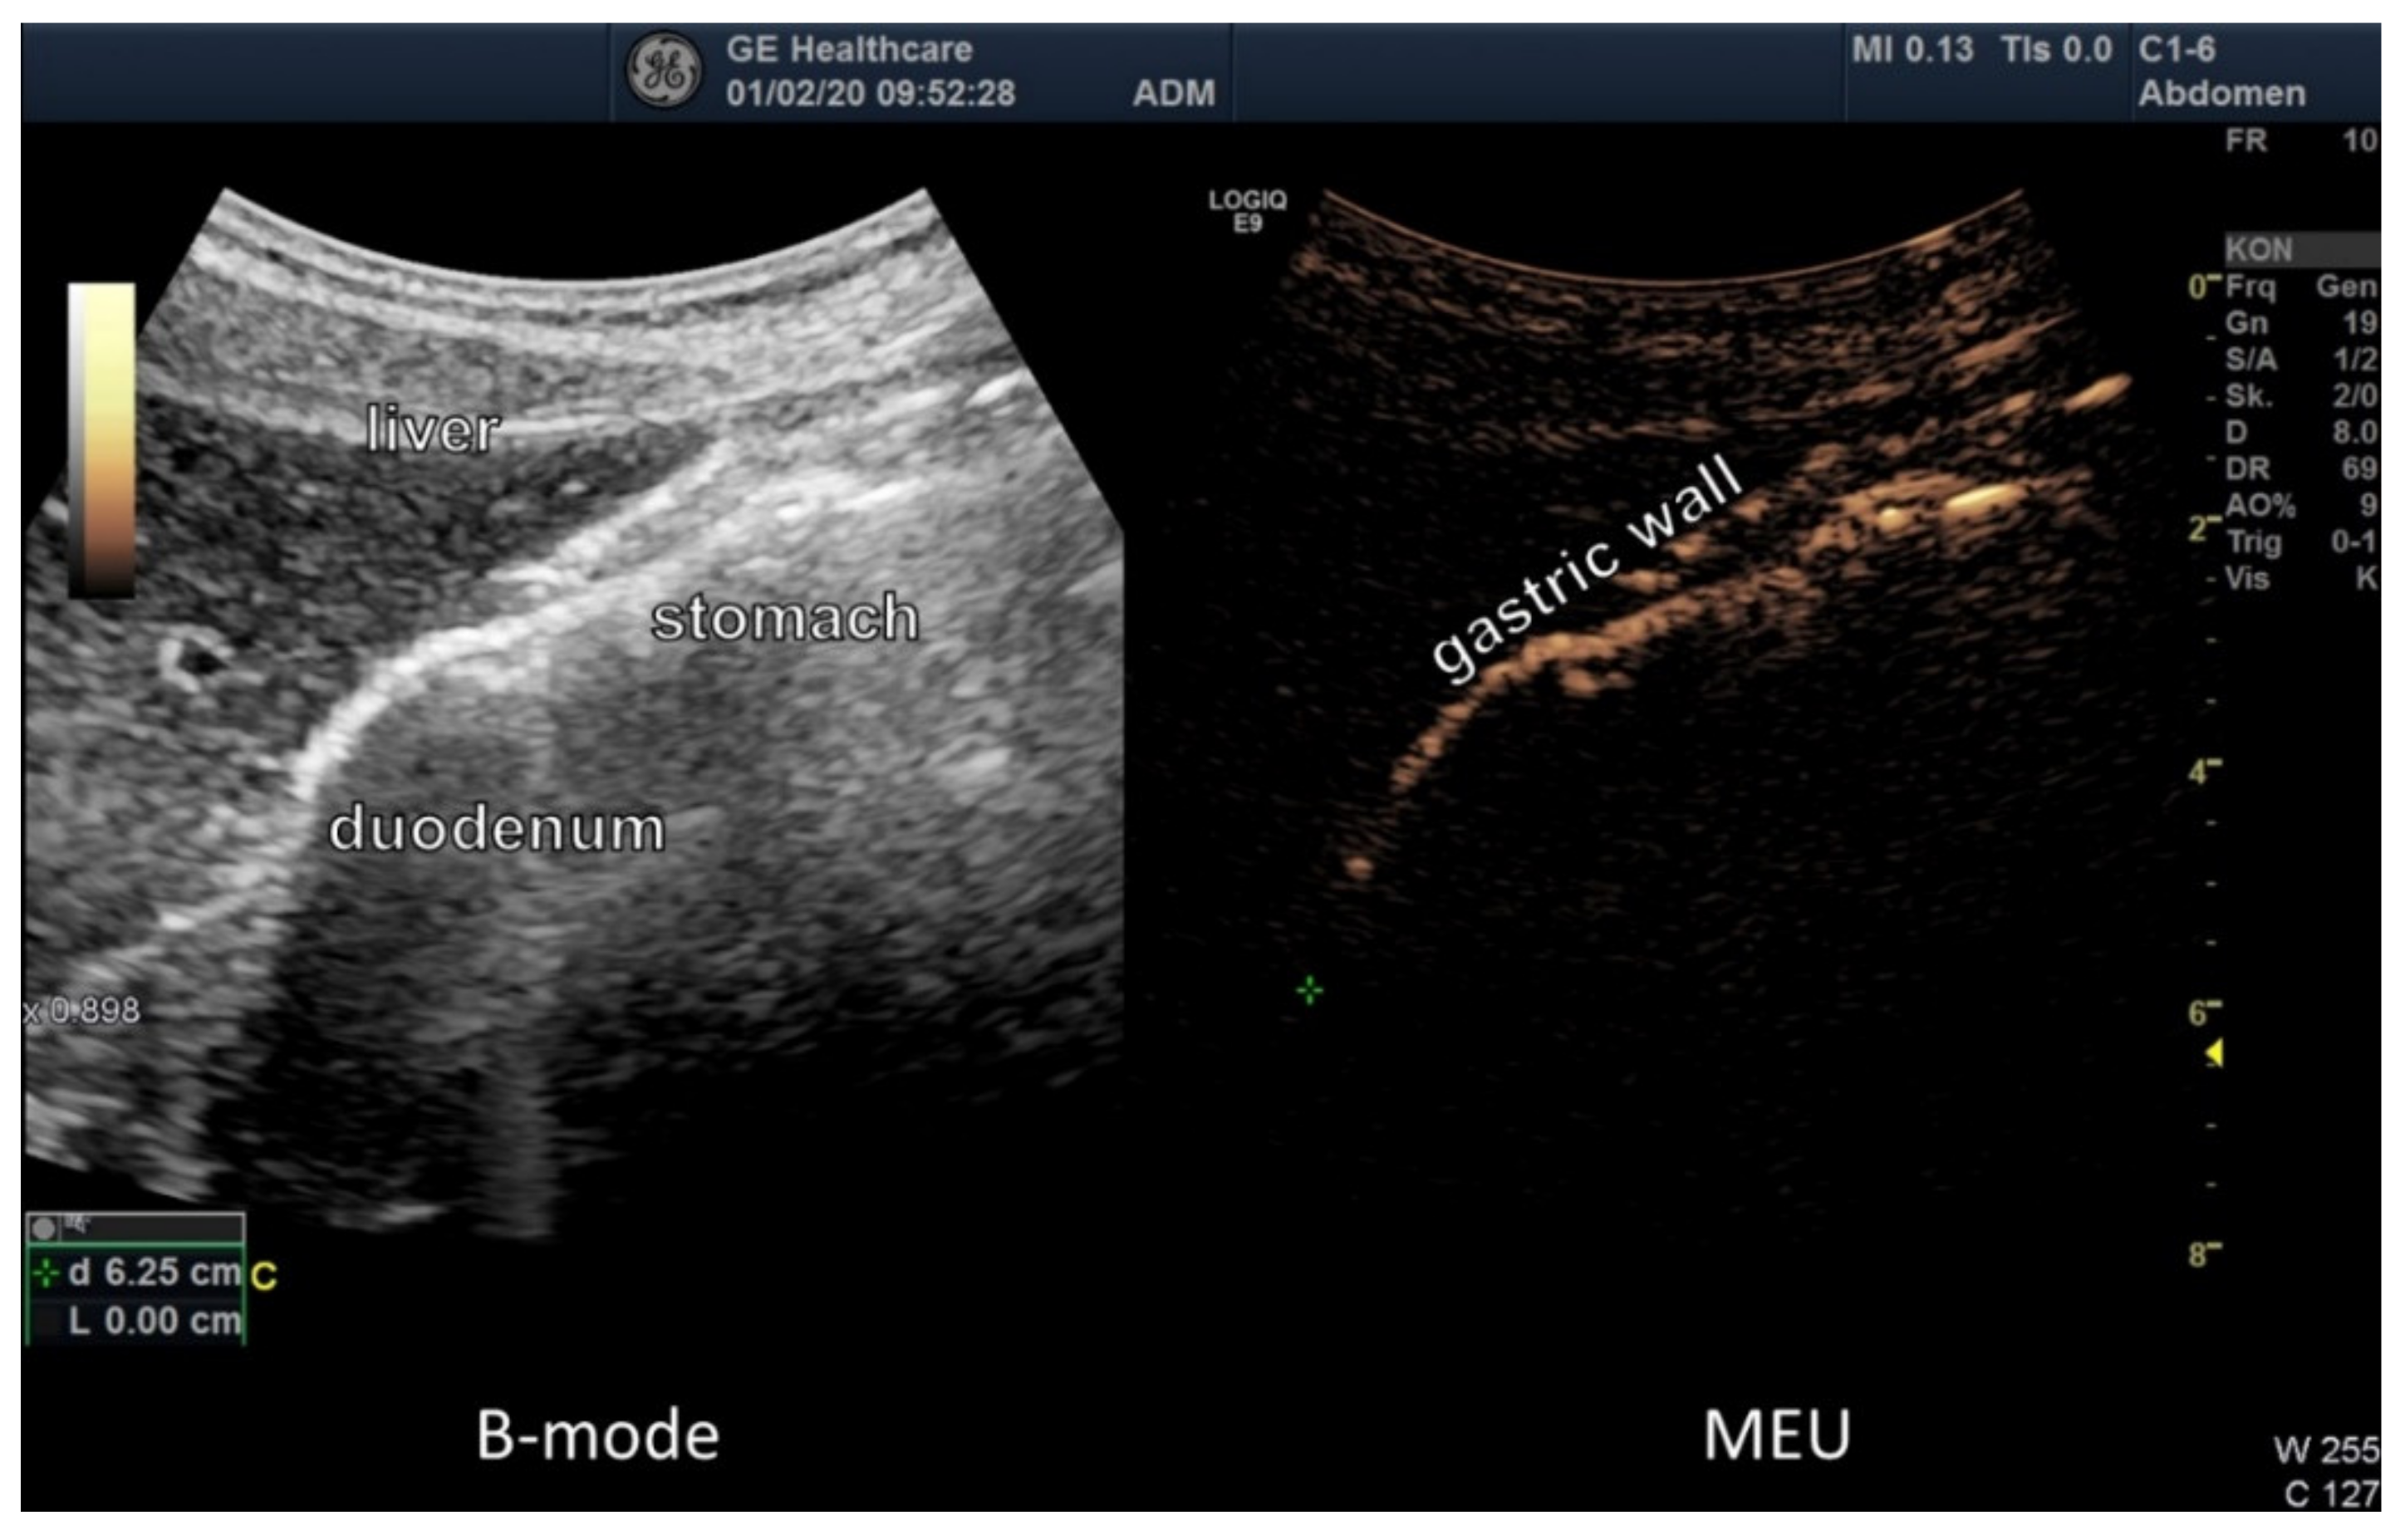

2.4. Ultrasound Examination of Intestinal Absorption

3.3. Ultrasound Examination of Intestinal Absorption